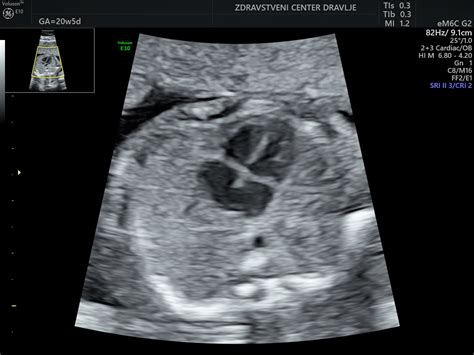

Diagnoza prazne gestacijske vrečke se postavi predvsem z ultrazvočnim pregledom.

- Transvaginalni ultrazvok: Ta metoda omogoča natančnejši prikaz zgodnjih nosečniških struktur. Običajno se izvaja med sedmim in devetim tednom nosečnosti, ko bi moral biti zarodek že viden. Če na ultrazvoku v tem času vidimo le gestacijsko vrečko ustrezne velikosti, vendar brez vidnega zarodka in srčnega utripa, je diagnoza verjetna.

- Merjenje velikosti gestacijske vrečke: Če gestacijska vrečka doseže premer 22 mm ali več, brez vidnih znakov zarodka ali srčnega utripa, je možnost za nadaljnji razvoj nosečnosti zelo majhna.